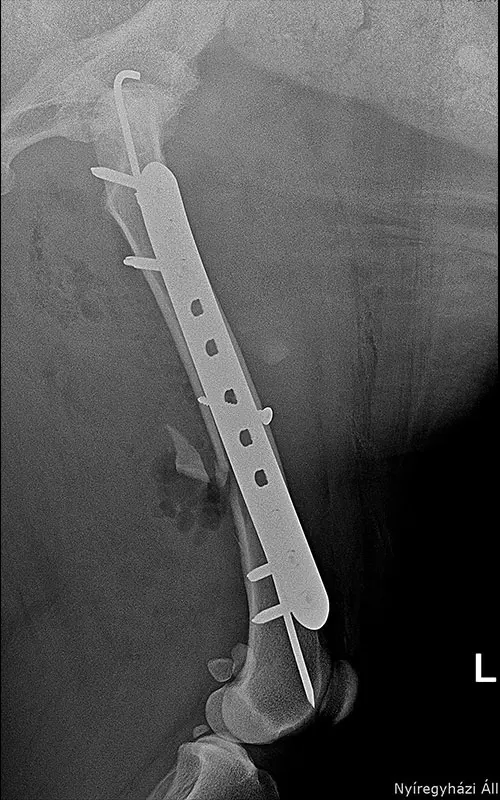

Combination of polyaxial locking plating and medullary pinning to treat multiple unstable fractures

It is a common case where long tubular bones suffer multiple fractures and there is no bone lying on top of each other after repositioning that would aid in stability after fixation. The K-wire-and-plate combination already known during DCP plating can also be used for locking plating:

- Among locking systems, only the polyaxial system is fully suitable for this task, because during the insertion of srews the medullary nail can be bypassed (cf. in monoaxial systems, if the nail is under the plate hole, no screw can be inserted in that hole).

In our case, a 10-year-old labrador is involved in a car accident and his left femur and right tibia are severely injured. The dog had difficulty moving anyway due to severe hip arthrosis. During one surgical narcosis, K-pin - polyaxial locking plating was applied to both bones, the larger fragments were also fixed with 1-1 lag screws.